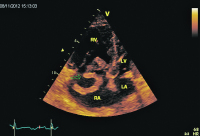

Septum

Abbildung 3: Parasternaler Querschnitt. Diastolische und systolische Abplattung des Septums als Hinweis auf eine rechtsventrikuläre Druckbelastung („D-Sign“). RV: rechter Ventrikel; LV: linker Ventrikel; IVS: intraventrikuläres Septum.